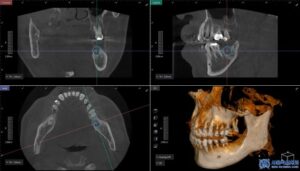

환자분은 좌측 아래쪽 어금니가 없는 상태였고,

오랫동안 방치되어 치조골(잇몸뼈)의

변화가 일부 있었습니다.

하지만 다행히도 임플란트를 식립하기에

충분한 골량이 유지되고 있었고,

무절개 방식으로 빠르게

임플란트를 진행할 수 있었습니다.

무절개 방식은 컴퓨터 분석을 통해

미리 임플란트의 식립 위치를 시뮬레이션하여,

수술 시 오차를 줄여주는 방법입니다.

수술 가이드를 활용하여 정확한 위치에

임플란트를 심기 때문에,

잇몸을 절개할 필요 없이 간편하고

안정적인 수술이 가능합니다.